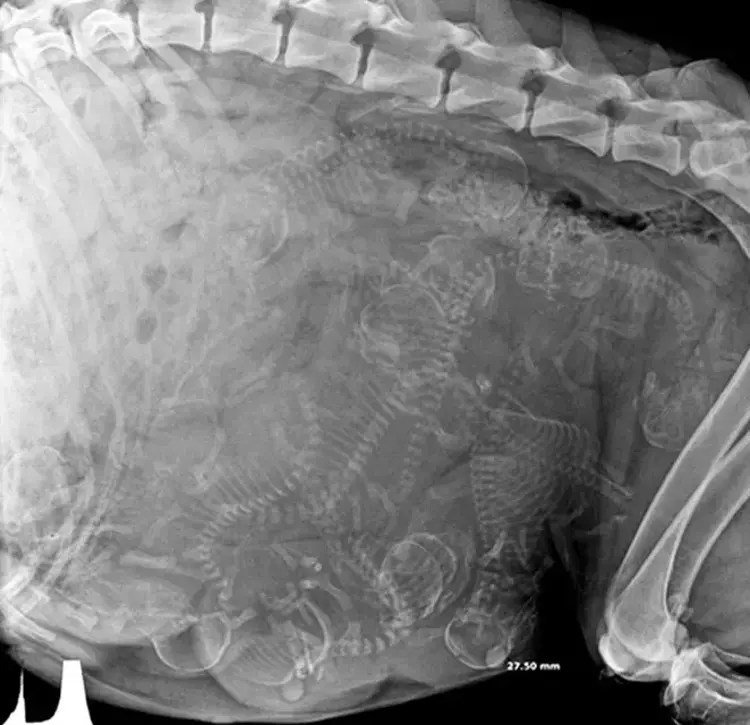

Kediniz kooperatif ise, kalp veya karın üzerinde ultrason yapmak için anestezi veya sedasyon gerekmez. Clueless republican bimbo insults warren and hillary, calls them (video). Kedi doğumu hakkında bilgiler.kedim doğurdu.kedi doğumu nasıl gerçekleşir? Lee drake | son güncelleme:

Bugün kedim pofuduk ile bebeklerini görmek için veteriner'e gittik ve ultrason ile yavrulara günlerdir merakla beklediğiniz luna'nın ultrason videosu yayında. Bununla birlikte, biyopsiler alınacaksa, prosedür sırasında evcil hayvanınızın. Metal, akrilik ve plastik kedi ultrason arasından ve. Hamile hayvanların i̇nanılmaz ultrason görüntüleri anne karnındaki bebeklerin ultrason görüntülerini hepimiz.